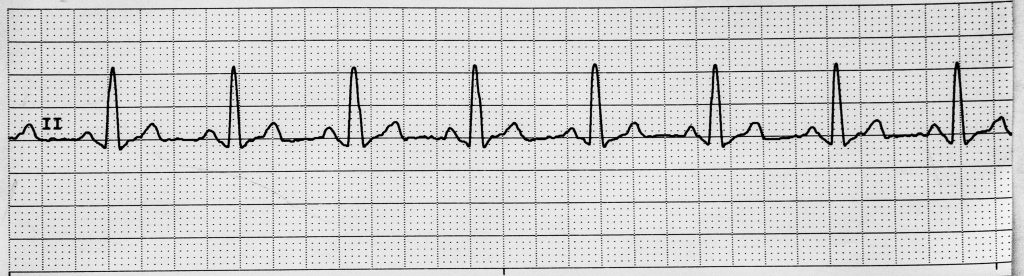

Rhythm #1 of 20